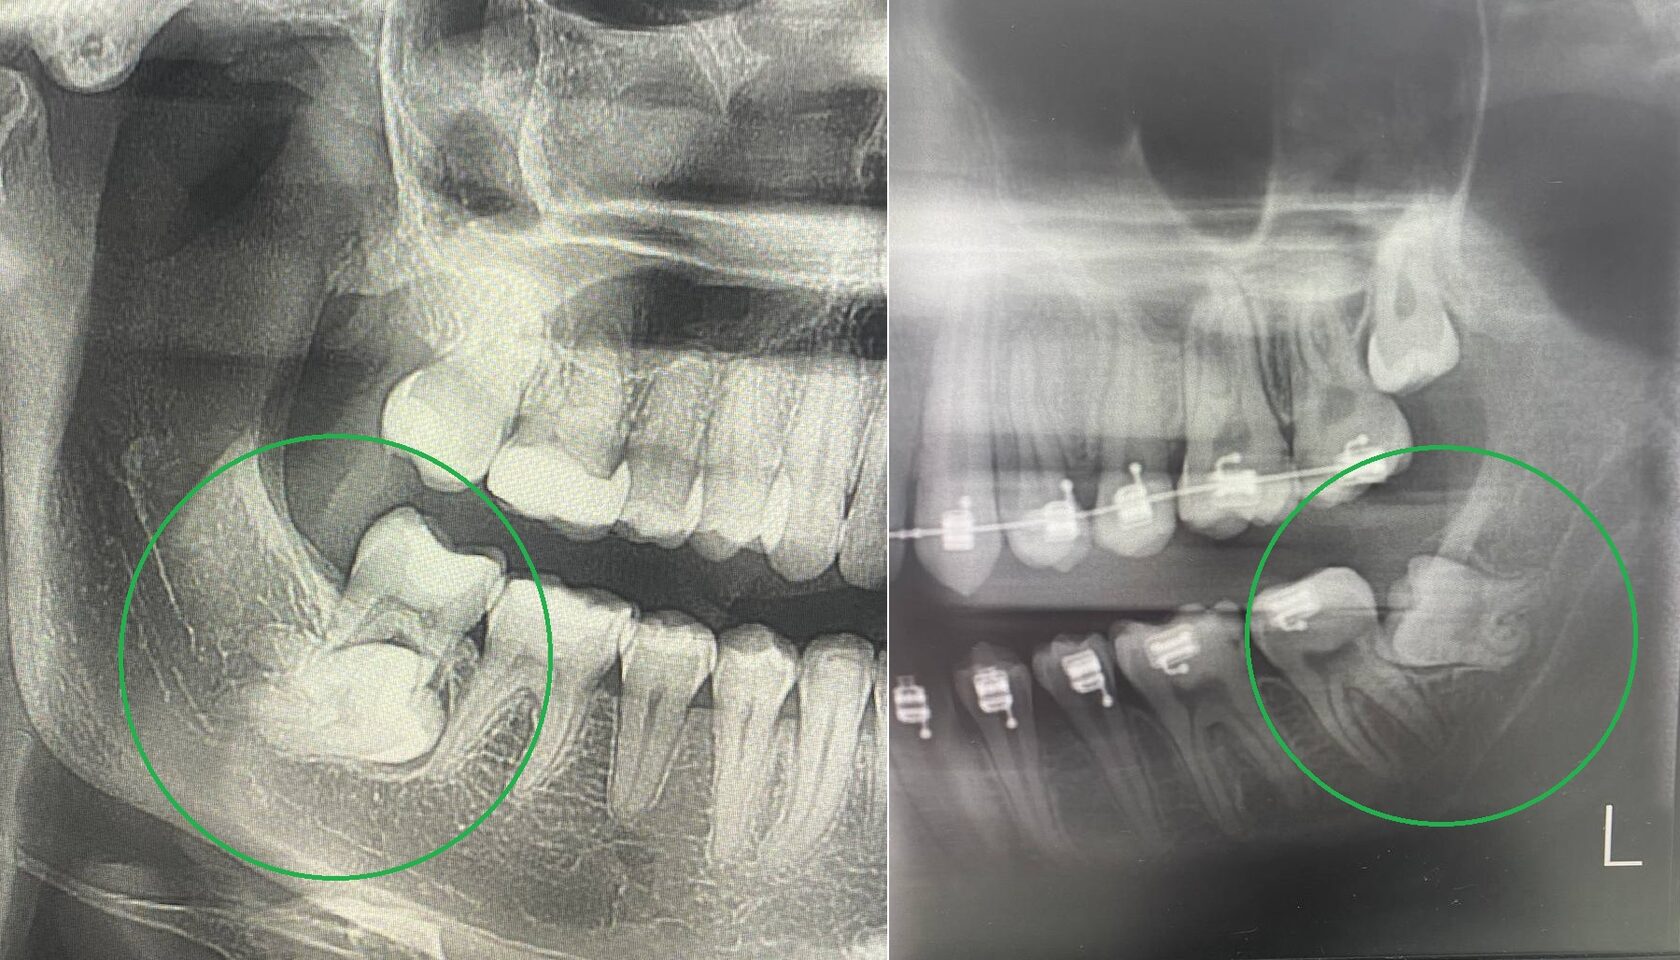

Дентальная галерея: ретинированный зуб клык и его лечение

Раздел: Компас решений